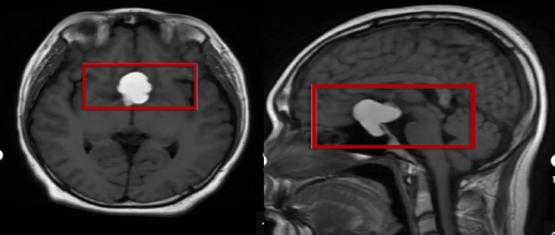

“因颅内鞍区肿瘤导致视力下降的病人并不少见。”金丽文医生解释说,颅内鞍区占位最常见的是垂体瘤和脑膜瘤,通常进展较缓慢,患者可能在不知不觉中丧失视力。许多患者在早期可能只有单侧视力下降,随着肿瘤的增长,可能会压迫到视神经,导致双侧视力受损。在视力缓慢下降的过程中,有些患者以为自己是年龄偏大,眼睛“老化”或者“老花眼”引起的;还有的近视患者以为是“近视度数加深”导致的,虽然前往医院就诊,但可能因为在疾病早期,除了视力异常外,没有其他眼部异常体征表现而漏诊。早发现早治疗,解除鞍区占位对视神经的压迫,可以大大提高视力恢复正常的可能。

孟冠军医生进一步说明。“很多患者认为视力问题就一定是眼睛本身的疾病,实际上,视觉通路从眼球一直延伸到大脑枕叶,任何一个环节出现问题都可能导致视力下降。特别是当视力下降与视野缺损同时出现时,我们必须警惕颅内病变可能,如垂体瘤、颅咽管瘤、脑膜瘤等,这些病变压迫视交叉或视神经,都会引起相应的视觉症状。”